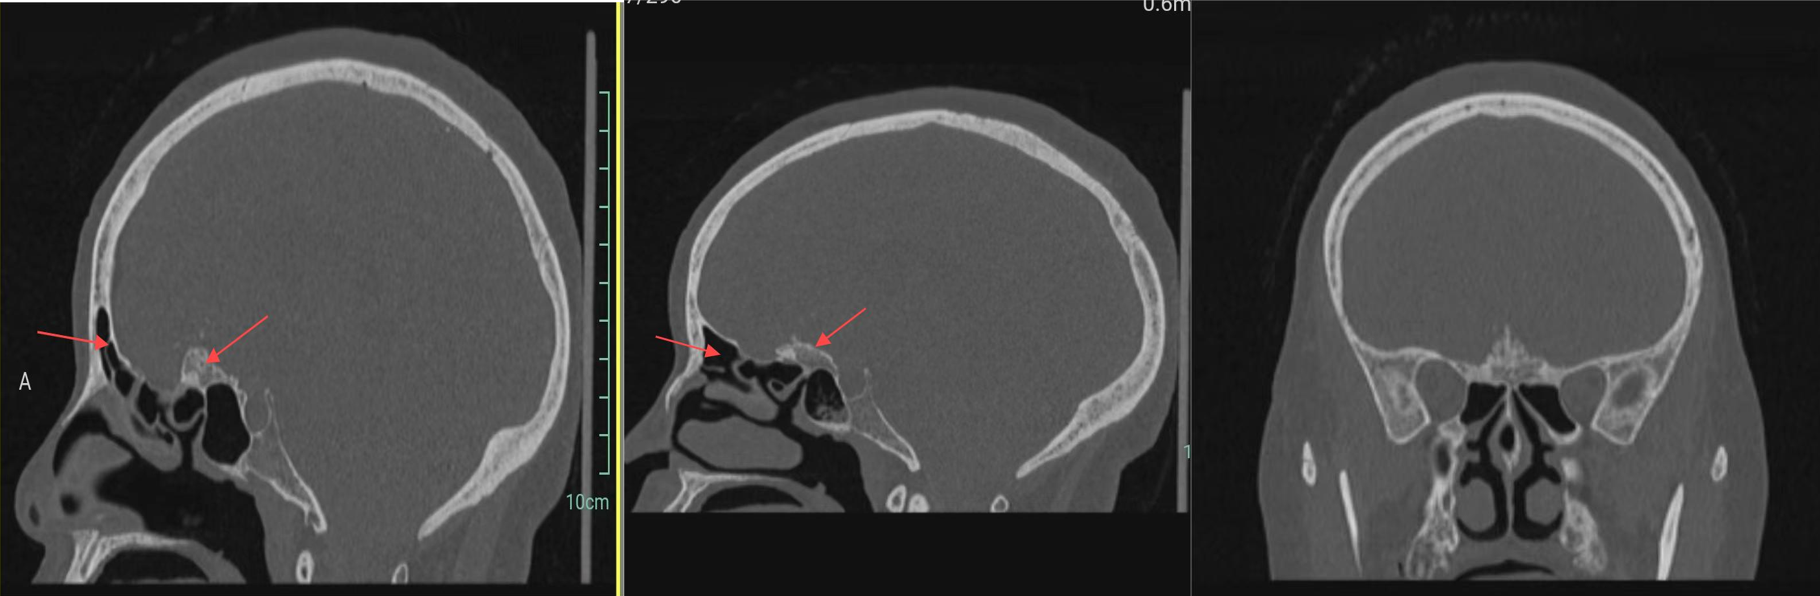

颅脑CT:前颅底占位性病变,颅底骨质增生,瘤内钙化,周围脑组织水肿。

颅骨冠矢状位重建示前颅底骨质明显增生,额窦发达。